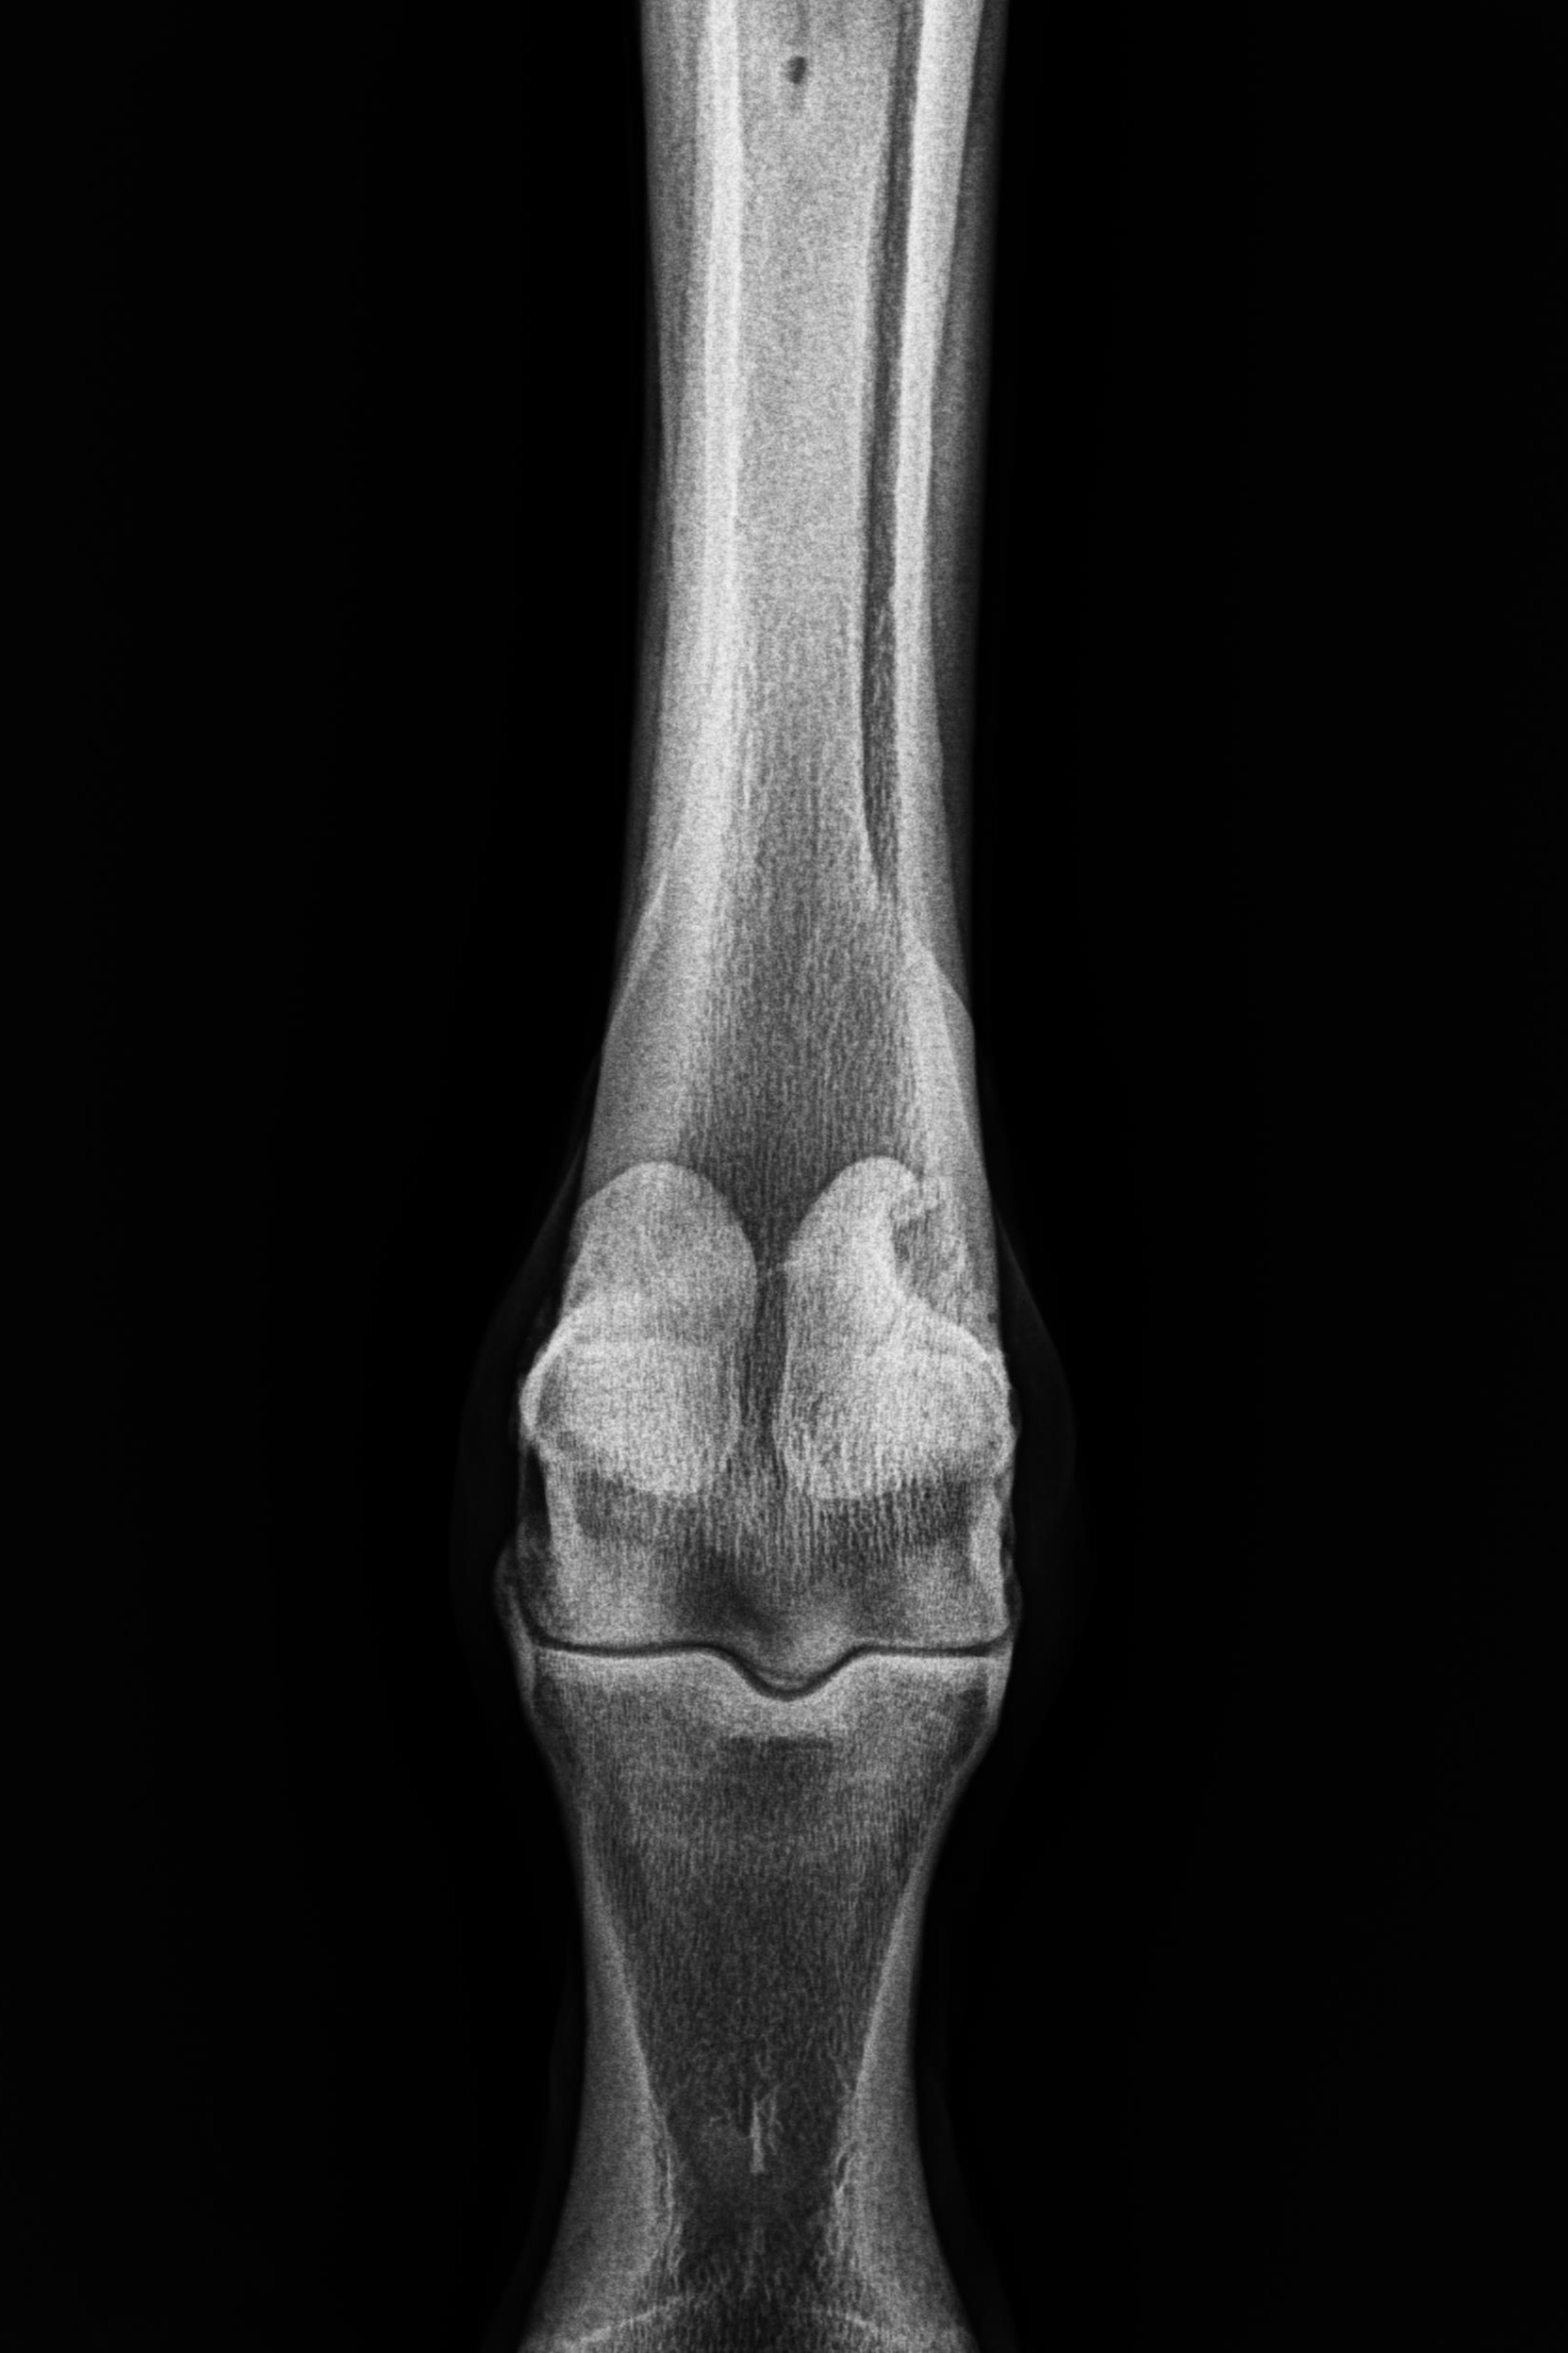

そんな状況の中、1月9日にレントゲン検査を受けると「左前肢外側の種子骨のボーンシスト」が原因と判明しましたので、サラブレッドオークションへ出品とさせていただきます。現状のままでは競走馬としてのデビューは難しいかも知れません。皆様には現状をご理解いただき、事前に獣医検査を受ける等、ご納得をいただいた上でのご検討、ご入札をお願いし、現状渡しのノークレーム、ノーリターンでお願いいたします。

セールの後からお預かりして来ましたが、レントゲン検査を受けて獣医から「このまま調教を進めたら骨折するリスクが大きい」との所見でした。競走馬は勿論ですが、現状のままでは乗馬としても厳しいと思います。(Team百馬力・原翼氏)